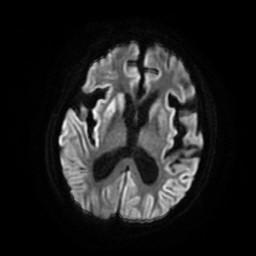

查体:神清,问之不答,四肢僵硬,左下肢屈曲,查体不能合作,双侧瞳孔等大等园,直径约3mm,光反射可,眼球运动、眼震等检查不合作,口角左偏,左侧鼻唇沟浅,肌张力高,肌力、共济、感觉检查均不能配合。辅助检查:颅脑DWI示:双侧尾状核头和豆状核信号增高,双侧大脑半球脑回皮质信号增高。视频脑电图:重度异常脑电图,背景节律无枕区优势,全导周期性双相波或三相波间断重复出现,意识模糊期间全导双相或三相波间断重复发放,脑脊液常规及生化、培养未见明显异常,脑脊液14-3-3蛋白送检未回。